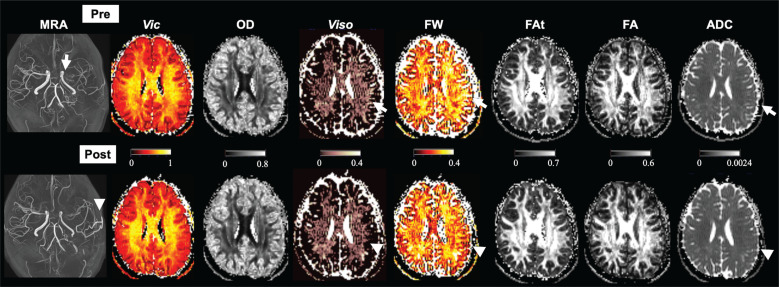

Methods: Multi-shell diffusion MRI (neurite orientation dispersion and density imaging and free water imaging using a bi-tensor model) was performed in 15 hemispheres of 13 adult patients with MMD (11 female, mean age 37.9 years) who had undergone revascularization surgery as well as age- and sex-matched normal controls. Parameter maps of free water and free-water-eliminated neurites were created, and the regional parameter values were compared among controls, patients before surgery, and patients after surgery.

Results: The anterior and middle cerebral artery territories of patients showed higher preoperative free water levels (P ≤ 0.007) and lower postoperative free water levels (P ≤ 0.001) than those of normal controls. The change in the dispersion of the white matter in the anterior cerebral artery territory correlated with cognitive improvement (r = -0.75; P = 0.004).